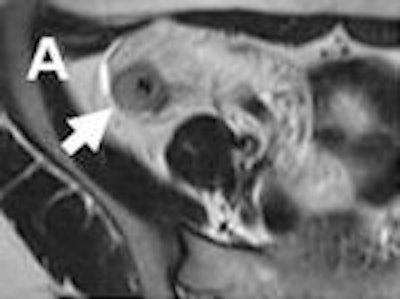

Because of superb spatial resolution, CTE is a good choice for establishing the presence and extent of active inflammatory disease. Mural stratification characterized at CTE is the most sensitive finding for active inflammatory disease, according to Dr. Khaled Elsayes, an associate professor of radiology at MD Anderson Cancer Center in Houston. Mural stratification can be appreciated by its trilaminar appearance, with enhanced outer serosal and inner mucosal layers and an interposed submucosal layer of lower attenuation.

A prominent vasa recta, often referred to as a "comb sign," and increased mesenteric fat attenuation are the most specific features of active Crohn's disease described by CTE.

Though MRE also can establish these findings, its capabilities extend to water-sensitive, T2-weighted imaging that differentiates between active inflammation and fibrosis. Active inflammation on MRI is characterized by bright areas of the bowel wall on T2-weighted imaging, whereas fibrosis is characterized by a hypointense presentation and also a T2-weighted sequence.

Dynamic gadolinium-contrast enhancement also aids the assessment of bowel wall pathology, with active inflammation revealing itself from early mucosal enhancement followed by delayed enhancement of the rest of the bowel wall. Fibrosis is characterized by an absence of enhancement of the mucosa, according to Gee.